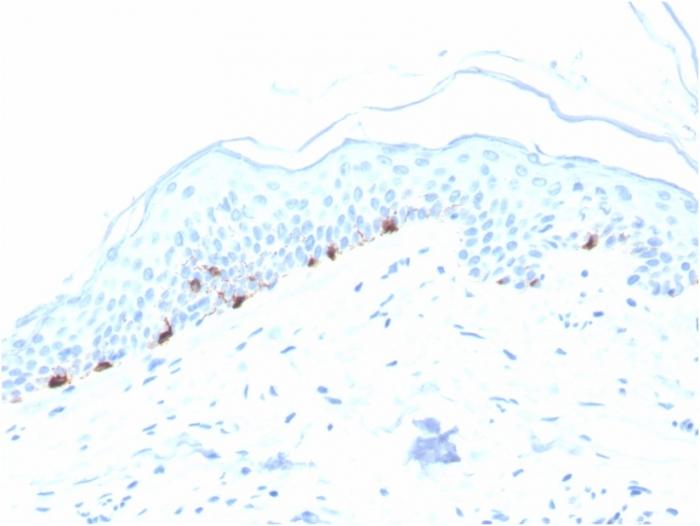

Reacts with a 75 kDa melanocyte-specific gene product, identified as Tyrosinase-related protein-1 (TRP-1). It is involved in melanin synthesis. TRP1 is present on the melanosomal membranes of melanoma, normal melanocytes and nevi. Recent evidence suggests that TRP-1 is involved in maintaining stability of tyrosinase protein and modulating its catalytic activity. TRP-1 is also involved in maintenance of melanosome ultrastructure and affects melanocyte proliferation and cell death. Primary antibodies are available purified, or with a selection of fluorescent CF® Dyes and other labels. CF® Dyes offer exceptional brightness and photostability. Note: Conjugates of blue fluorescent dyes like CF®405S and CF®405M are not recommended for detecting low abundance targets, because blue dyes have lower fluorescence and can give higher non-specific background than other dye colors.

SK-MEL-23, SK-MEL-19, SK-MEL-30, SK-MEL-37 cells. Human skin or melanoma tissues (IHC).

IHC, FFPE (verified)

IHC (FFPE) (verified)